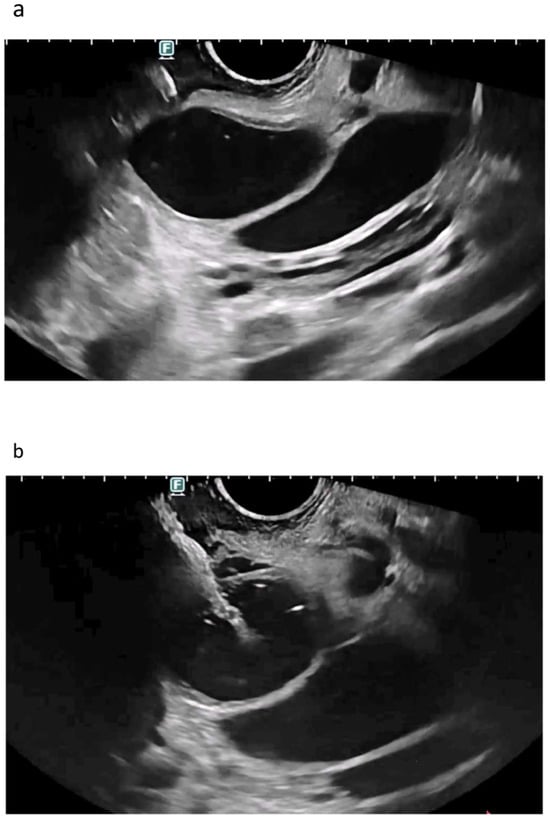

3.1.1. EUS-BD of the Bile Duct

3.1.2. EUS-GBD

3.2. Arguments against EUS-Guided Drainage

7. Do We Need Cystotomes?

8. Do We Need Bougies?